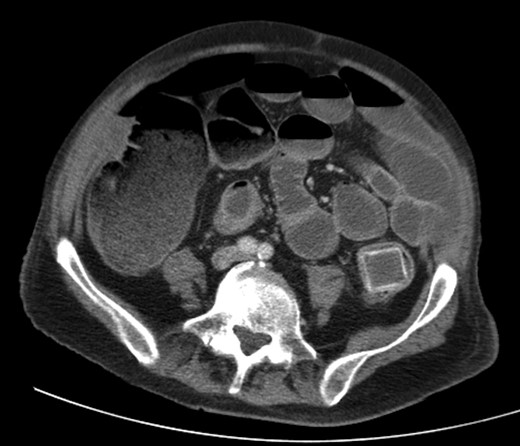

A 92-year male, with no significant co-morbidities apart from peptic ulcers, was admitted with 6 days of obstination. On examination he was dehydrated, with a hugely distended abdomen but no signs of peritonitis. Blood showed features of dehydration and plain abdominal X-ray demonstrated both small and large bowel dilatation, but no obvious causal pathology. A contrast-enhanced computed tomography scan revealed a 2.5-cm partially calcified gallstone impacted at the descending colon-sigmoid junction (Fig. 1). There was no stricture or diverticular disease distal to the stone. A cholecysto-colic fistula could be seen (Fig. 2), with a further smaller gallstone in the caecum (Fig. 3). The offending gallstone could be seen incidentally in the gallbladder on imaging 3 years previously (Fig. 4).

Cholecysto-colic fistula, with a thick-walled, dilated, gallbladder.